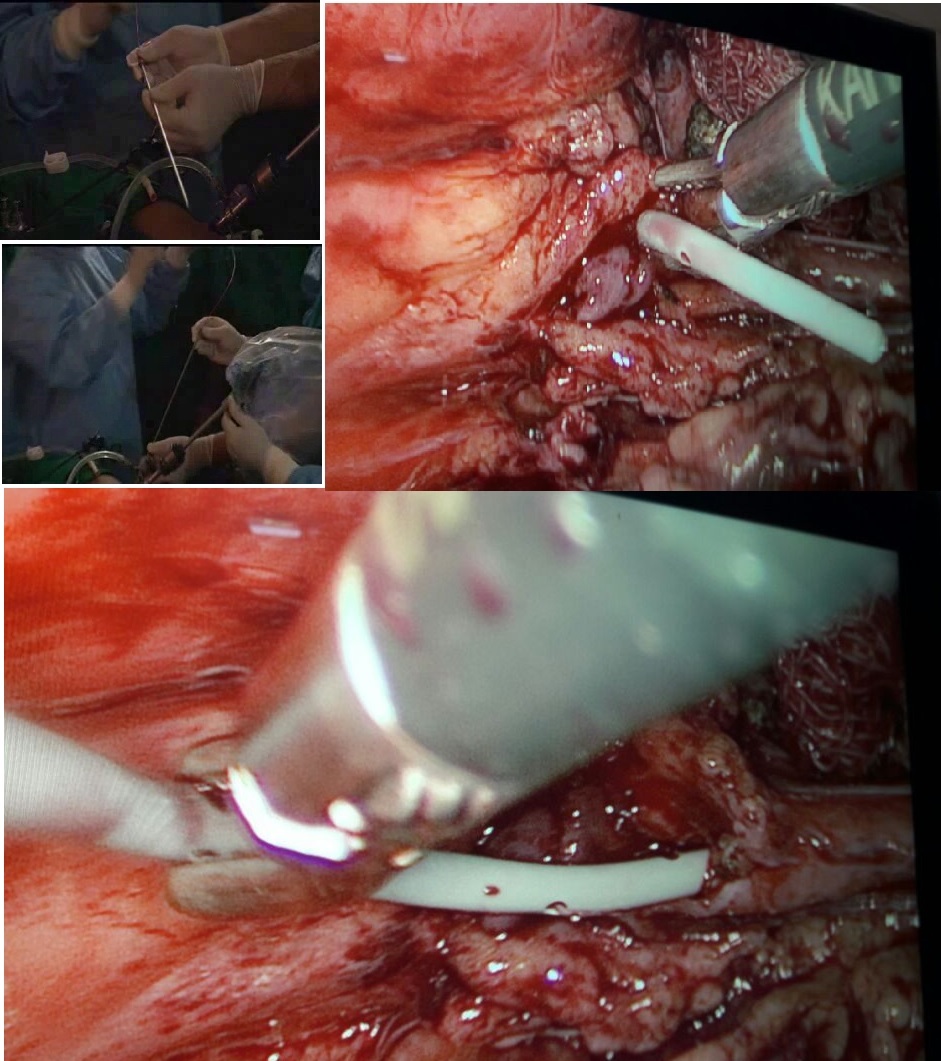

Aims and Objectives. To study the safety and efficacy of retroperitoneal laparoscopic pyelolithotomy in retroperitoneal renal stone. We compared the results of laparoscopic and open surgery in terms of easy accessibility, operative period, renal injuries, and early recovery.

Methods. This prospective study was conducted on renal pelvic stone cases from January 2009 to February 2016 in Suchkhand Hospital, Agra, India. The study included a total of 1700 cases with the diagnosis of solitary renal pelvic stones. In group A - 850 cases - retroperitoneal laparoscopic pyelolithotomy was performed, while group B - 850 cases – underwent open pyelolithotomy.